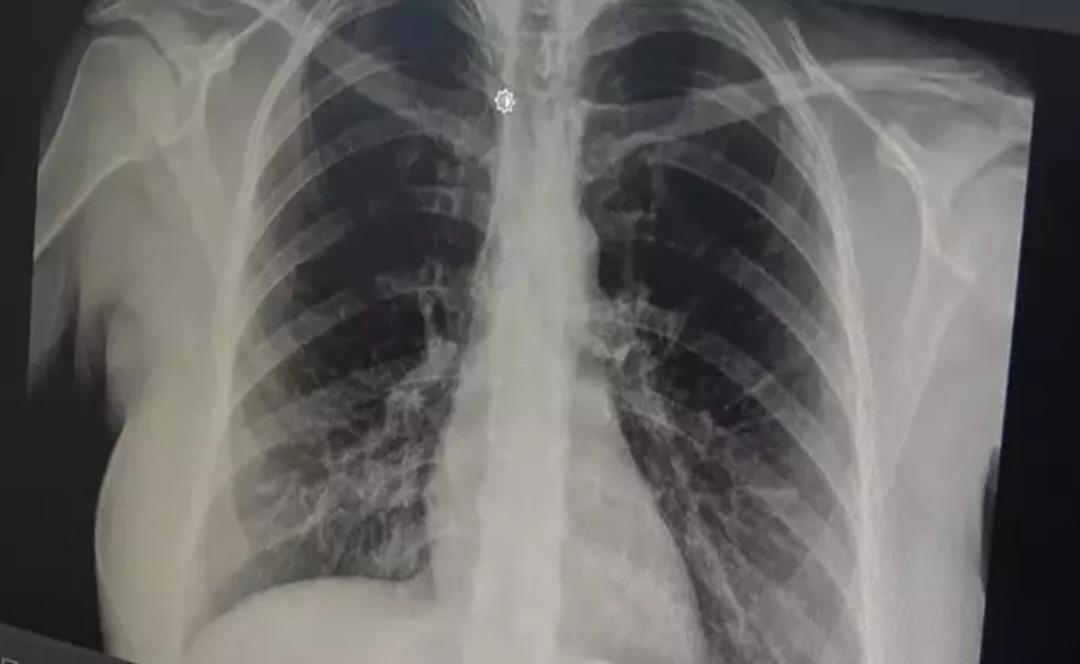

prof. Akut bronşitin solunum yolu virüslerinin neden olduğu bir hastalık olduğunu belirten Dr. Özlü, şöyle konuştu: “Günümüzde çok sık gördüğümüz bir hastalık. Genelde hastalar şöyle tarif ediyor: 'Öncelikle boğazım ağrıyordu, boğazım ağrıyordu. hafif ateş, burun akıntısı, hapşırma, geniz akıntısı ve öksürük: “2-3 gündür göğsümdeydi. Nefes alırken acı hissediyorum. İçeride bir çalı varmış gibi görünüyor. Nefes aldığımda göğsüm oraya sıkışıyor” çünkü aslında gerçek bu. “Bronşit, solunum yolu virüslerinin neden olduğu bulaşıcı bir hastalıktır. Bu enfeksiyon üst solunum yollarıyla sınırlı olmayıp alt solunum yolları ve bronşları da etkiliyor” dedi.

Akut bronşitin en önemli belirtisinin öksürük olduğunu vurgulayan Prof. Dr. Tevfik Özlü, “Kuru öksürük veya balgamlı öksürük şeklinde kendini gösterebiliyor. Bazen belirti daha çok hırıltılı solunum ve nefes darlığı şeklinde hissedilebiliyor. Yüksek ateş genellikle herhangi bir rahatsızlığa neden olmaz ancak bazen bakteriyel enfeksiyonlar da ortaya çıkabilir” dedi.

Bronşitin genel olarak hafif bir hastalık olduğunu ancak belirtilerin artması durumunda doktora başvurulması gerektiğini belirten Özlü, şöyle konuştu: “Altta yatan kronik bir hastalık, astım veya KOAH obstrüktif hastalığı gibi bir akciğer hastalığı varsa, kronik hastalığın akut alevlenmesidir. Buna hastalık eşlik edebilir ve genel akut bronşit nefes darlığı, hırıltı, halsizlik, yorgunluk ve yüksek ateş gibi ciddi belirtilerle ortaya çıkabilir veya altta yatan kronik bir hastalık varsa ve belirtilerde alevlenme varsa mutlaka doktora başvurunuz.” Genel olarak hafif, tedavi edilebilir bir hastalık olduğunu söyleyebilirim” dedi.